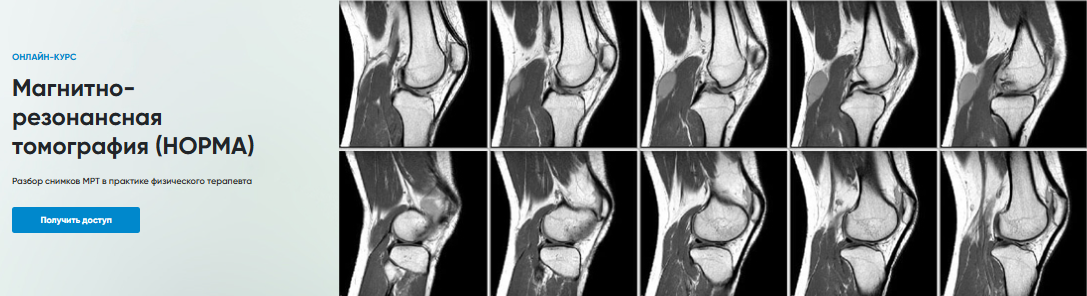

[Rehab Science] Магнитно-резонансная томография. Норма (Андрей Богатырев)

Магнитно-резонансная томография (НОРМА)

Разбор снимков МРТ в практике физического терапевта

Программа

1. МРТ Коленного сустава

2. МРТ Голеностопного сустава

3. МРТ Запястье

4. МРТ Локтевого сустава

5. МРТ Плечевого сустава

6. МРТ Поясничного отдела позвоночника

7. МРТ Тазобедренного сустава

8. МРТ Шейного отдела позвоночника